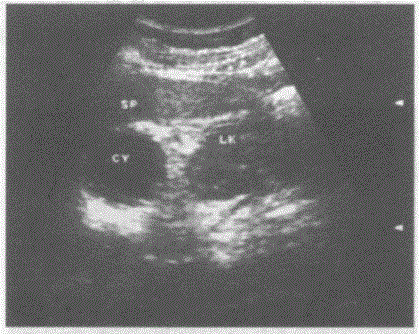

临床资料:女,55岁,常规体检。超声综合描述:左肾上极与脾之间可见3.4cm×4.0cm圆形无回声区,包膜完整,后方声加强,CDFI:内未见动静脉血流...

问题 临床资料:女,55岁,常规体检。 超声综合描述:左肾上极与脾之间可见3.4cm×4.0cm圆形无回声区,包膜完整,后方声加强,CDFI:内未见动静脉血流信号。 超声提示:

选项 A.左肾囊肿 B.左肾上腺囊肿 C.脾囊肿 D.副脾

答案 B